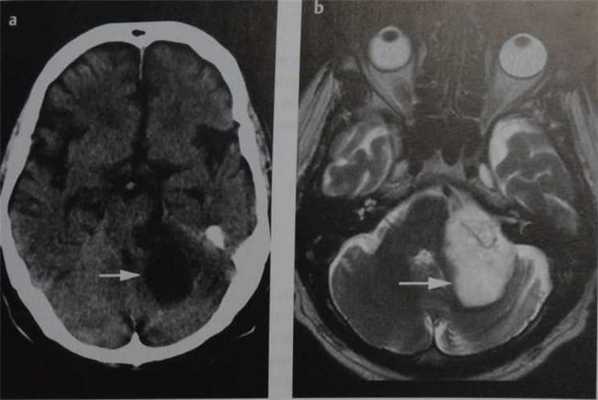

Субтенториальная эпидермоидная киста и арахноидальная киста полюса левой височной доли. КТ, аксиальный срез (а), МРТ, аксиальное Т2-ВИ (b) и аксиальное Т1-ВИ (с) после введения КС. Ни КТ, ни традиционные МР-изображения не позволяют четко дифференцировать эпиде моидные кисты от арахноидальных. Подобно кисте паутинной оболочки, эпидермоидная киста выглядит гиподенсной (а) или гиперинтенсивной (b) и гипоинтенсивной по отношению к паренхиме головного мозга (с) и не накапливает КС (с, стрелка). Однако МР-сигнал в эпидермоидной кисте неоднородный.